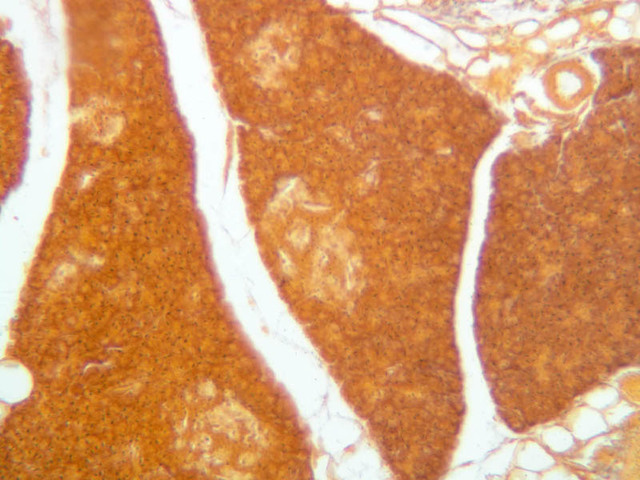

Although H & E staining permits ready identification of the islets of Langerhans, it does not permit differentiation of the various cell types that comprise the islets (B-36, H&E [10x, 20x, 40x-labeled]). There are no slides in the class collection that permit identification of all of the cell types of the endocrine pancreas. However, the sections on slides B-37 and B-40 permit specific identification of two cell types. Slide B-37 has been stained by the aldehyde fuchsin technique, which lends a magenta coloration to the granules of the insulin-producing B-cells. All other cells in the islets stain a dirty orange color (B-37 [10x, 20x, 40x] [10x, 20x, 40x]). Most of these orange-colored cells are the glucagon-secreting A-cells; however, you should bear in mind that somatostatin-secreting D-cells, as well as APUD cells that secrete pancreatic polypeptide are also scattered about the islet. The section on slide B-40 has been prepared by a silver impregnation method that renders some of the APUD cells in the islets (which appear as “clear cells” in ordinary preparations) dark brown or black (B-40 [10x, 20x, 40x]).